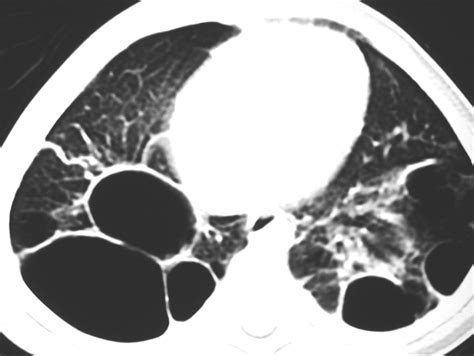

Because blebs in lungs are usually invisible on a standard physical examination, doctors rely heavily on imaging technology to detect them and assess the extent of a pneumothorax if it occurs.

CT Scan (High-Resolution) Provides highly detailed images that can pinpoint the exact location and size of blebs.